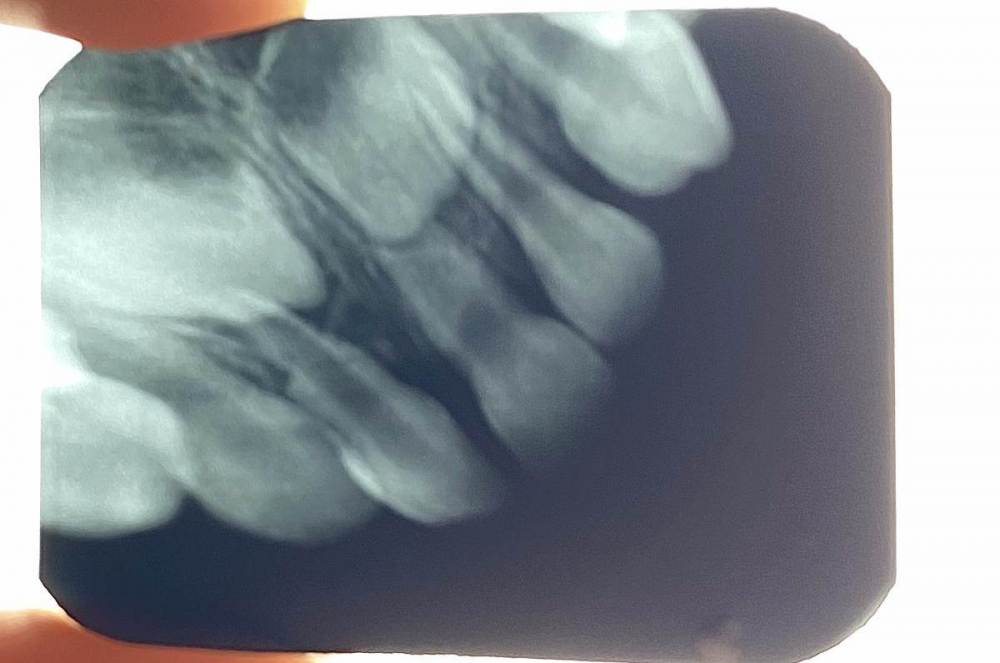

Julia1 Опубликовано 14 апреля, 2023 Поделиться Опубликовано 14 апреля, 2023 Добрый день, помогите пожалуйста разобраться. Ребёнок 2 года в конце января упал, зуб 5.1 пострадал, немного выбился в десну и как я поняла повернулся. Сделали контрольный снимок. Нужно ли с ним что-то сейчас делать? (Один врач говорит пролечить корневые каналы, второй - удалять, если появится свищ, припухлость или будет беспокоить ребёнка) Фото прилагаю Ссылка на комментарий

Julia1 Опубликовано 15 апреля, 2023 Автор Поделиться Опубликовано 15 апреля, 2023 @IvanK Зуб не беспокоит Фото зуба прилагаю Ссылка на комментарий